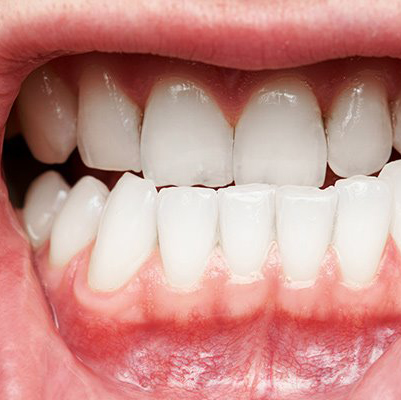

Healthy gums are firm, pale pink, and fit snugly around the teeth. With periodontitis, symptoms may include:

• Swollen or puffy gums

• Bright red, dusky red, or purplish gums

• Tender gums (pain when touched)

• Gums that bleed easily (especially while brushing or flossing)

• Gum recession (teeth appearing longer than usual)

• New gaps or spaces developing between teeth

• Pus between teeth and gums

• Persistent bad breath (halitosis)

• Loose or shifting teeth

• Painful chewing

• Change in the way your teeth fit together when you bite